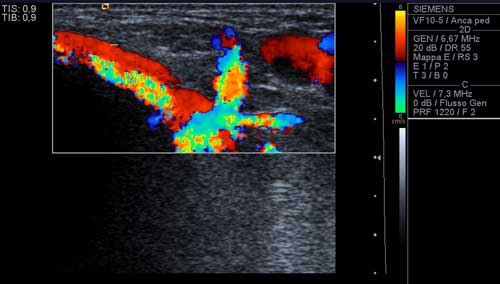

L�esame

ultrasonografico, condotto con sonda lineare da 10 MhZ, dimostrava,

nel sottocute del 1� spazio intermetatarsale del piede dx, la

presenza di una formazione rotondeggiante, con aspetto a clessidra

asimmetrica, rinforzo di parete posteriore, ben delimitata,

dimensioni 18 x 11 x 26 mm, con centro anecogeno e periferia

debolmente ecogena con parete esterna nettamente delimitata e vallo

interno irregolarmente sfrangiato (Figura 1), localizzata

immediatamente a valle della biforcazione della arteria pedidia nel

ramo plantare profondo e nella 1a metatarsale dorsale,

arteria che appariva decorrere, sia pure in maniera irregolare, lungo

la parete mediale della formazione (Figura 2)

Figura 1. Ecografia-scansione longitudinale con misurazione del diametro massimo. |

Figura 2. Componente vascolare della neoformazione a valle della biforcazione della arteria pedidia. Nello spessore dello strato pi� esterno si dimostrava la presenza di un flusso ematico bidirezionale (Figura 3) ![]() | |